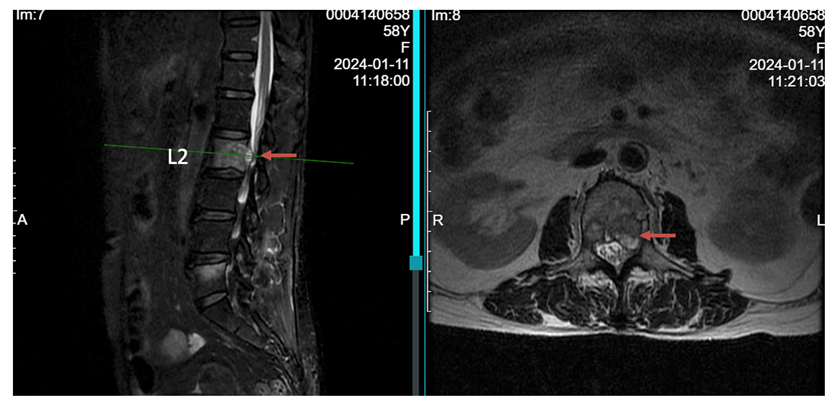

读片:CT及MRI检查提示,T2,L2,L5椎体骨质破坏,红色箭头所指为转移病灶所在位置,可见L2椎体病灶已侵犯后壁,突入椎管内。

患者为胸腰椎多节段的转移,且椎体病灶位置多位于后方,后壁已破损(T2,L2),因此不宜行椎体成形术(存在骨水泥渗漏至椎管风险)。

术后6月与术前MRI对比,红色箭头处可见术后6月椎体内肿瘤较术前明显缩小,突入椎管内情况有明显好转。